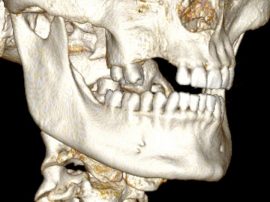

L’intervention chirurgicale consiste en une reconstruction osseuse du maxillaire ou de la mandibule avant la mise en place des implants dentaires par votre chirurgien.